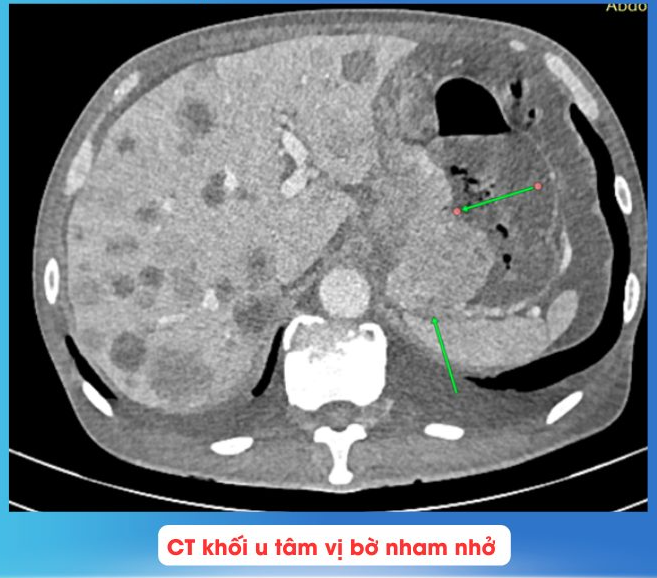

Dưới hướng dẫn của máy DSA, bác sĩ đã tiến hành chọn lọc đến nhánh nuôi khối u dạ dày, sau đó đã bơm tắc hoàn toàn nhánh này ngăn chặn việc xuất huyết. Bệnh nhân được tiếp tục theo dõi, sau 3 ngày bệnh nhân đã tiêu phân vàng, HGB tăng từ 3.3-> 4.7 -> 5.8-> 6 ->7.7 g/dl.

Hình ảnh mạch máu trước và sau can thiệp - Ảnh BVCC